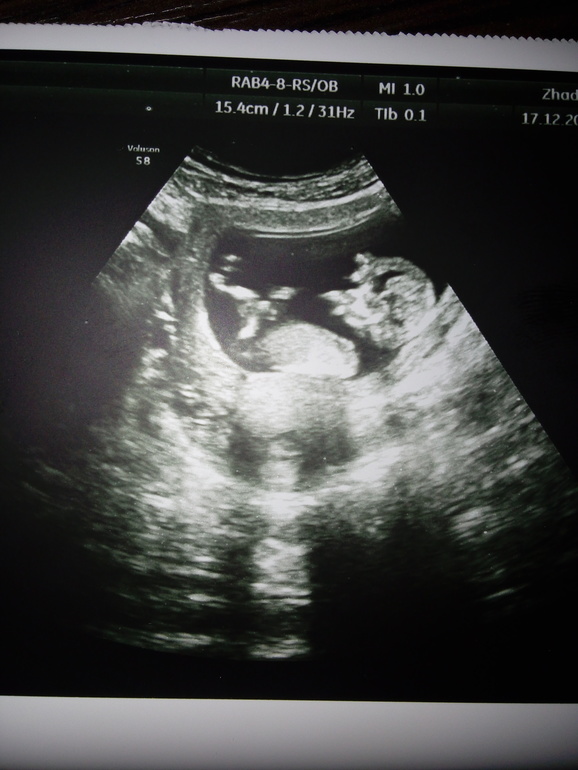

УЗИ 1й скрининг

Результаты: УЗИ, КТГ, доплера, скринингаСегодня сходила на 1й скрининг, все у малышастика хорошо , во всю машет ручками, открывает ротик, берет ручку в рот (как на фото УЗИ)

Одна ручка за головкой, вторая во рту)))